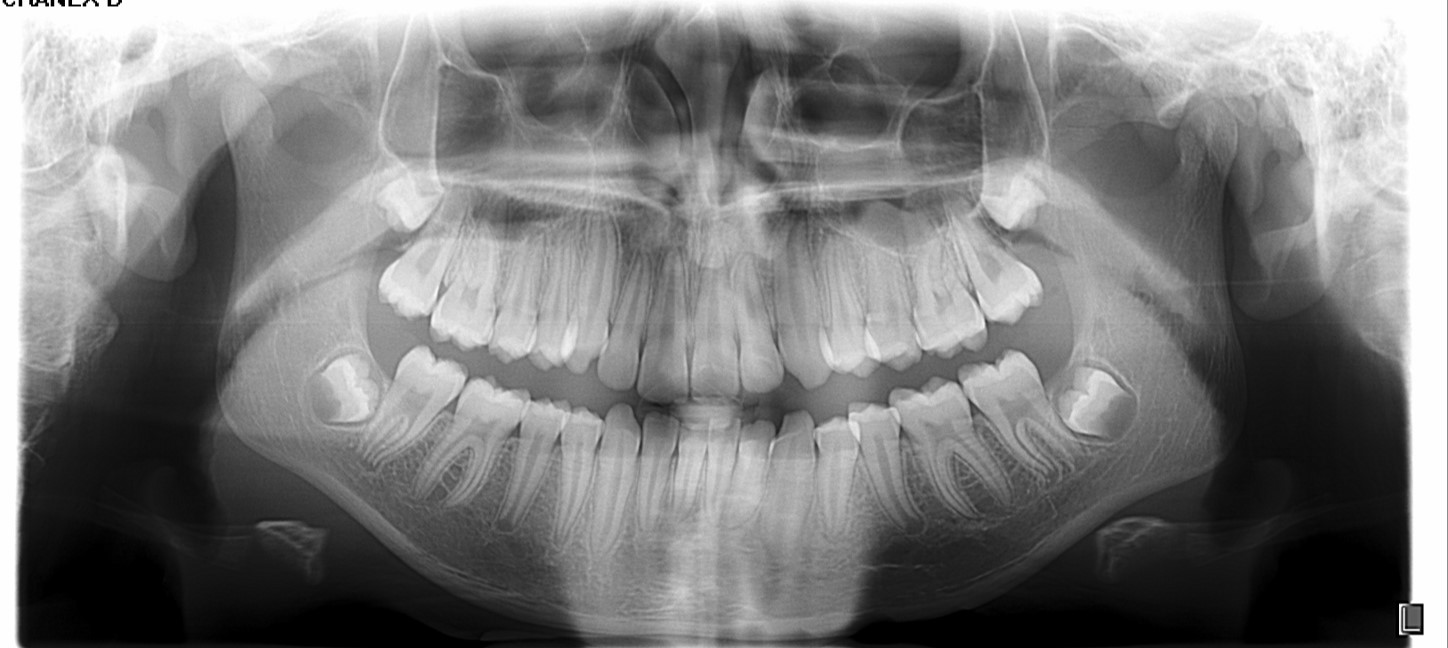

Chief complaint: We present the case of a 12-year-old female patient who came for an orthodontic evaluation, motivated by a family history of treatment. Clinical and radiographic analysis revealed a skeletal Class II malocclusion with molar and canine relationships also in Class II, moderate crowding in both arches, a deviation of the dental midline, and ectopic eruption of tooth 13. No functional issues with breathing or swallowing were observed, and oral health was generally good. A slight mandibular retrusion was noted in the soft tissue profile. A treatment plan was proposed using the Angel Aligner Pro system, aiming to correct dental misalignments and improve facial harmony through a minimally invasive, growth-adapted approach.

Clinical examination and diagnosis

- Woman ; 12/3 years

- Skeletal Class II

- Molar and canine Class II

- Upper and lower dentoalveolar compression

- Increased overjet and overbite

- Upper midline deviated 0,5 mm to the right

- Moderate upper and lower crowding